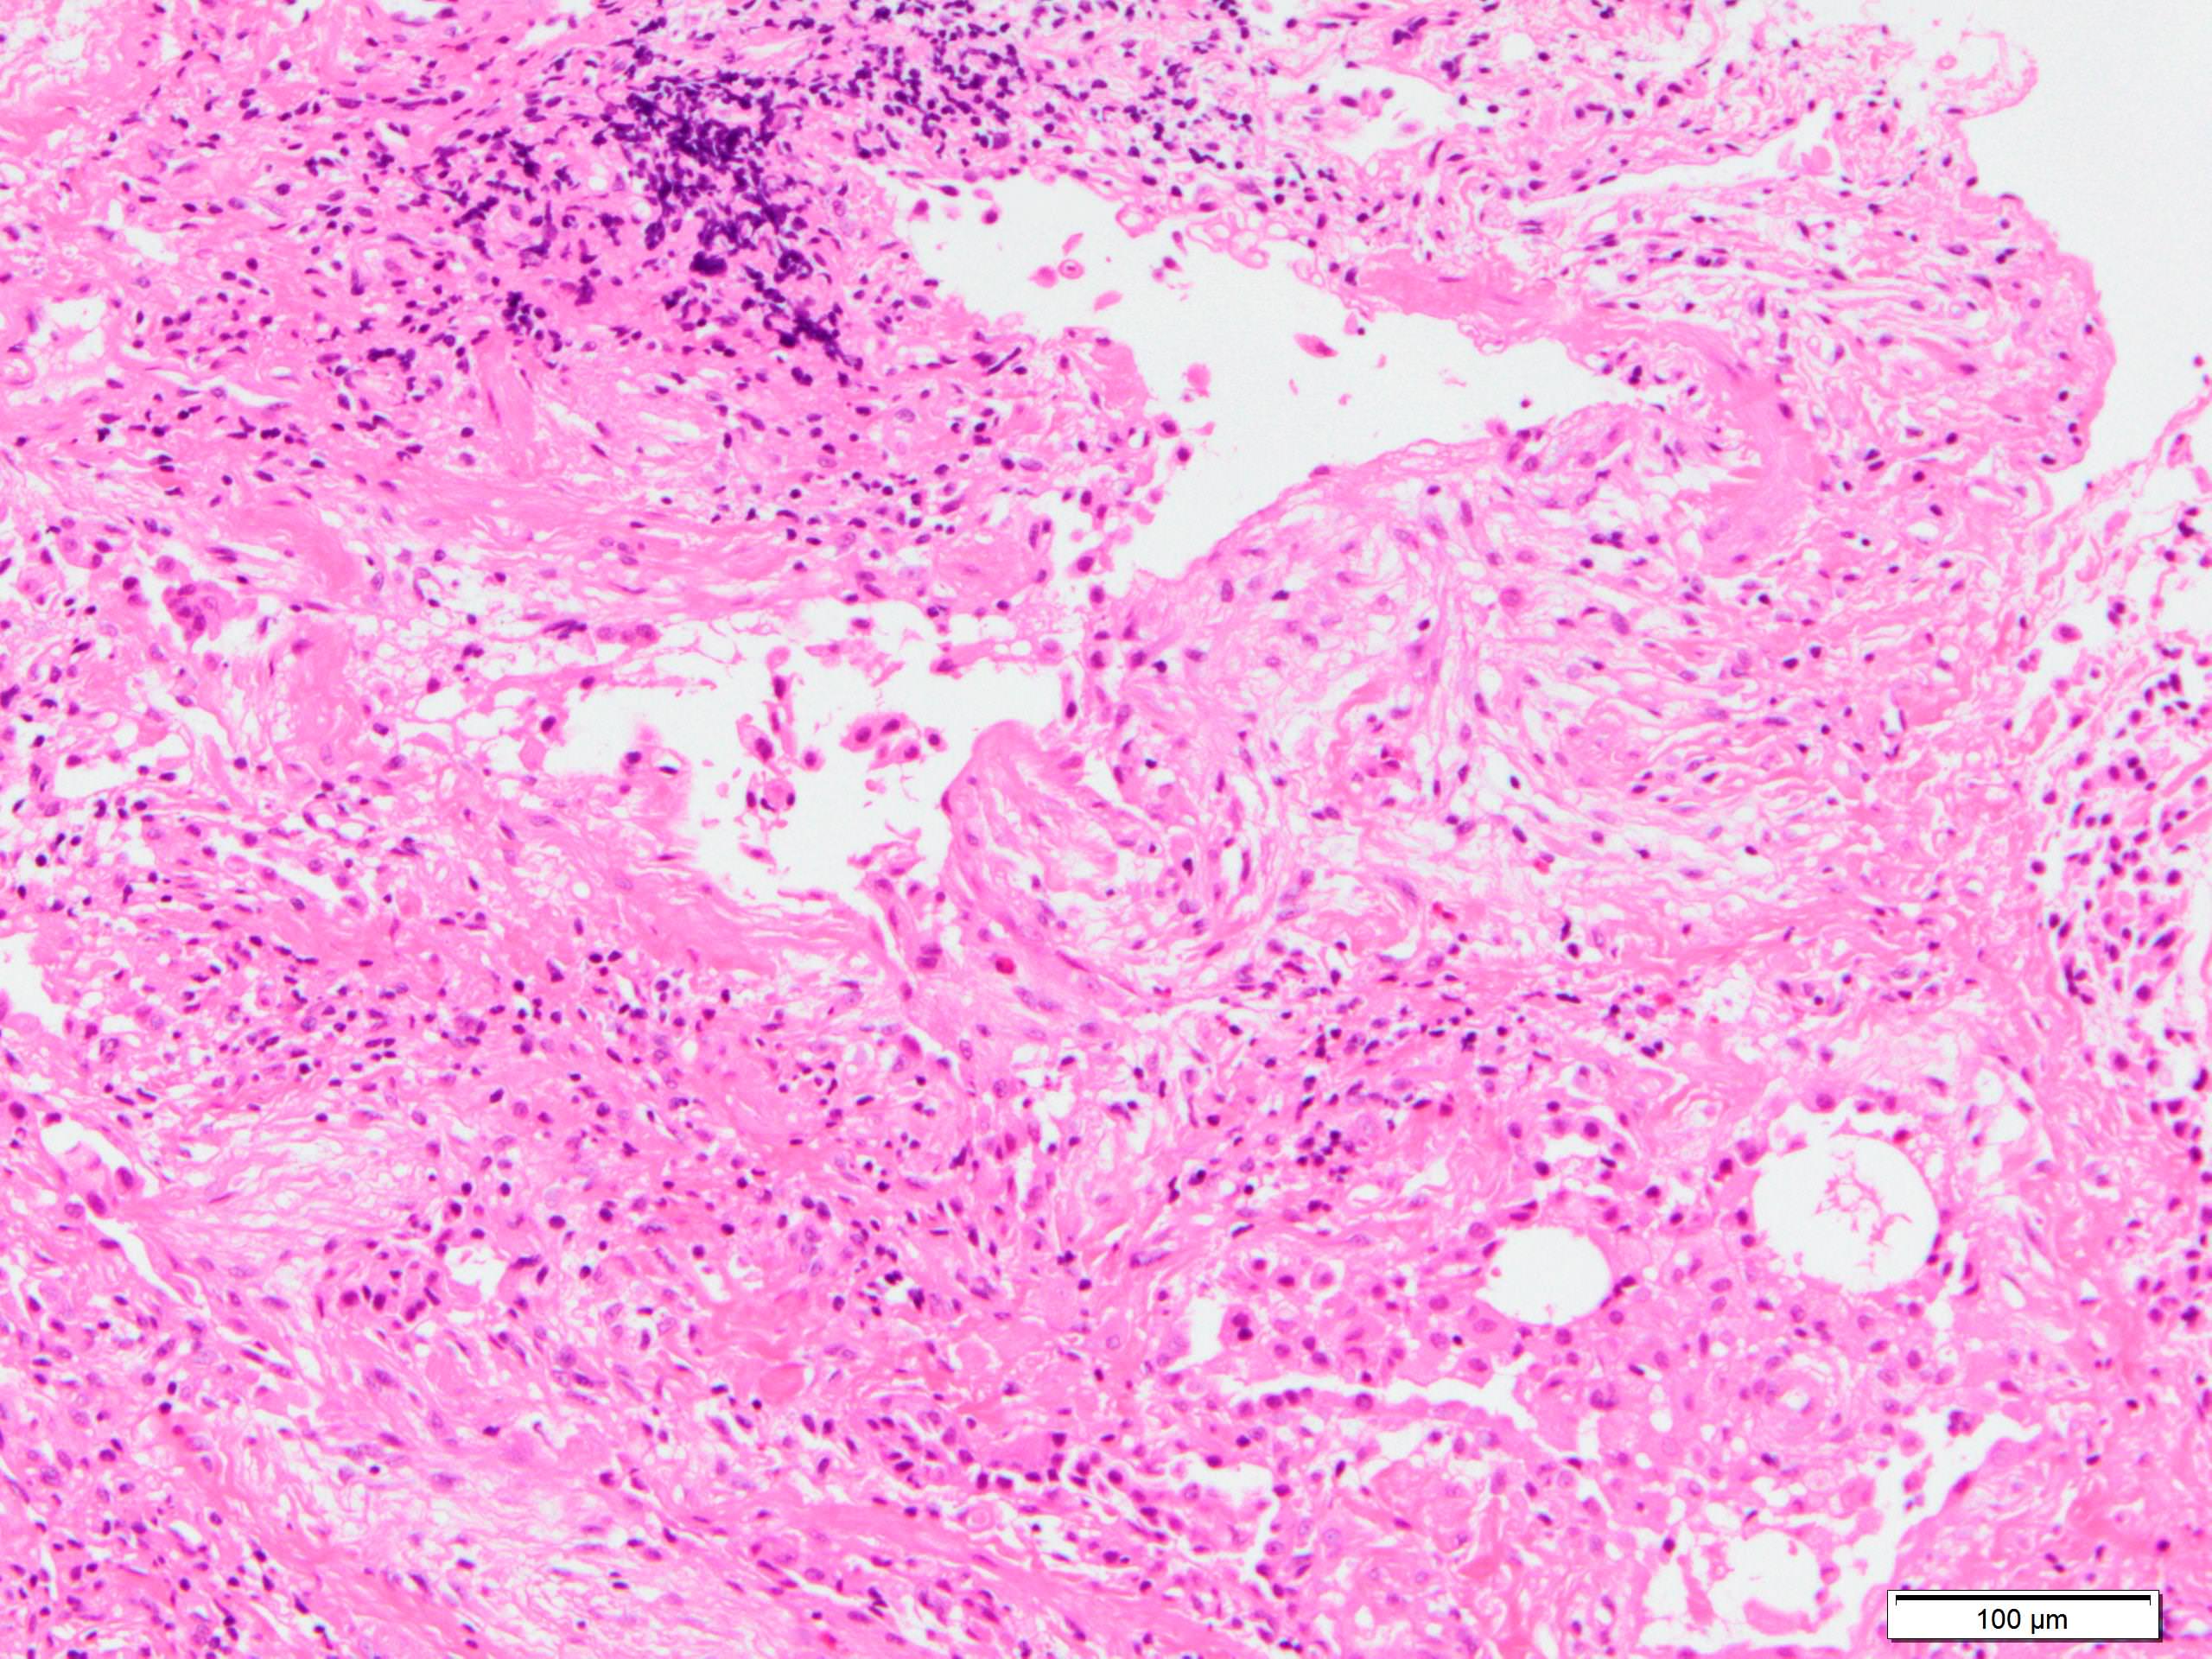

Microscopic (histologic) description

- Since there are few specific findings for NSIP pattern, it is essential to exclude other lung diseases on histology (Am J Respir Crit Care Med 2008;177:1338)

- Characteristic findings of NSIP pattern

- Diffuse and uniform inflammation ("temporal homogeneity") on low power of alveolar wall, bronchovascular bundles and pleura

- There are usually no normal alveolar walls in the affected lobules

- Cellular or fibrotic change

- Lymphocytic or plasmacytic infiltration

- Loose fibrosis

- Lung architecture is frequently preserved

- "Cellular NSIP" or "fibrotic NSIP" can be stated specifically in pathologist report

- Diffuse and uniform inflammation ("temporal homogeneity") on low power of alveolar wall, bronchovascular bundles and pleura

- It is quite rare to see pure NSIP on histology - typically there are focal findings of other interstitial lung disease (Histopathology 2014;65:549)

- Pertinent negative findings (Am J Respir Crit Care Med 2008;177:1338)

- UIP-like change

- Marked architectural distortion

- Dense fibrosis with smooth muscle hyperplasia or elastosis

- Fibroblastic foci

- Honeycomb change

- Hypersensitivity pneumonitis-like change

- Airway centered change

- Peribronchiolar metaplasia

- Granulomas or interstitial giant cells with cholesterol cleft

- Extensive organizing pneumonia (areas more than 20% of disease)

- Desquamative interstitial pneumonia-like change

- Aggregation of respiratory bronchiolitis macrophages in alveolar sacs and respiratory bronchioles

- Diffuse alveolar damage-like change

- Hyaline membrane

- Alveolar hemorrhage

- Lymphoid interstitial pneumonia-like change

- Marked and extensive infiltration of lymphocytes in alveolar wall

- Light chain restriction

- Smoking related interstitial fibrosis (J Clin Pathol 2013;66:882)

- Alveolar hyalinized septal thickening with little cellular infiltration

- Centriacinar emphysema

- UIP-like change

Microscopic (histologic) images

Contributed by Akira Yoshikawa, M.D.

Contributed by Akira Yoshikawa, M.D.